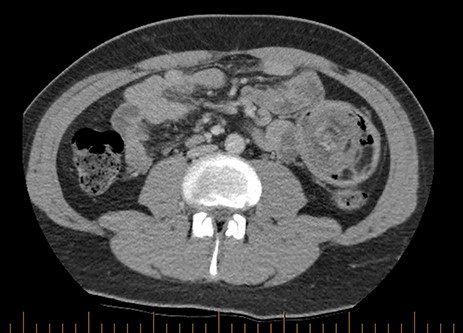

Prior to this presentation, the patient had already had an ultrasound examination and routine biochemistry performed, both unremarkable. Computed tomography (CT) imaging was performed at the time of his second presentation which demonstrated a very large intussusception in the left side of his abdomen with proximal jejuno-jejunal involvement, marked enlargement of the intussuscipiens containing the intussusceptum and an enlarged peri-gastric node measuring 17 × 14 × 14mm at the gastric cardia. There were no imaging features suggestive of ischaemic bowel or intestinal lipomatosis (see Figs 1 and 2).

Coronal view of CT imaging demonstrating a very large intussusception on the left side of the abdomen with proximal jejuno-jejunal involvement. Marked enlargement of the intussuscipiens containing the intussusceptum.